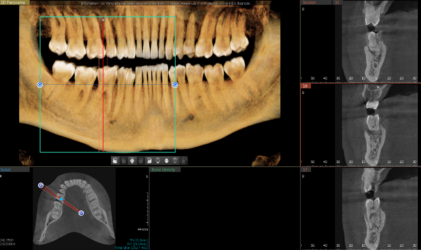

Hi! I have a case I wanted some feedback on. Pt is interested in replacing 24 and 25 with implants. I have attached the cbct below and was wondering what you guys think as far as tx planning. I wanted to place 1 implant with a cantilever for 24 and 25. How would you plan the case given the thin bone? Alveoplasty? GBR? Thank you